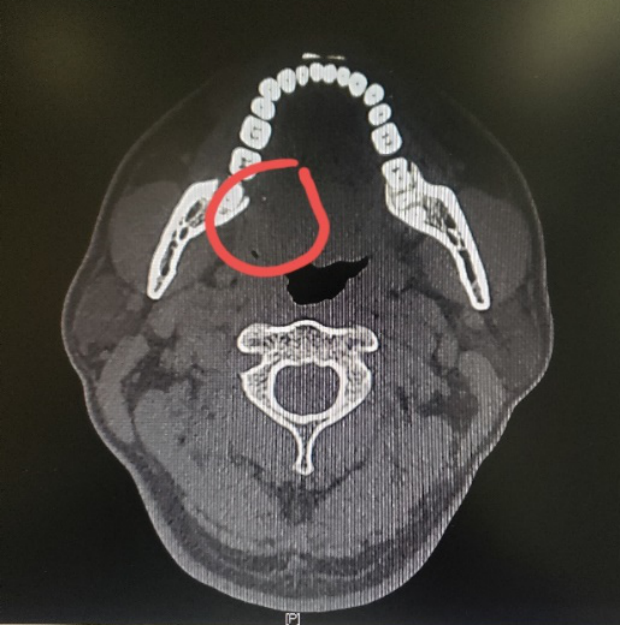

图一:病人的术前CT

图四:病人的术前MRI

那么这个异物包裹性脓肿里面到底是什么呢?我猜测要不是鸡骨,要不就是鱼刺,但鸡骨的话体积比较大,在CT上一般能看得出来,而且这么大的鸡骨插进舌头,病人的症状会非常明显,不会等到几个月后才来就诊。而鱼骨一般是很纤细的,在CT上是看不出来的,不过我们仔细看影像的话,还是可以在切面上发现小的阻射影的。